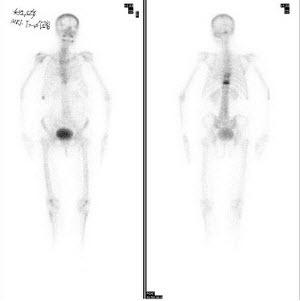

41、多项选择题

男,21岁,临床诊断胃癌,诉全身多处骨关节疼痛,行全身骨显像如图,对此影像下列描述正确的是()

A.胸12椎体放射性“冷区”

B.若同时X线检查为阴性则提示骨转移可能性大

C.“冷区”的出现一定表明骨转移

D.患者胸骨浓聚提示骨转移

E.胸12椎体可能存在肿瘤的骨髓浸润